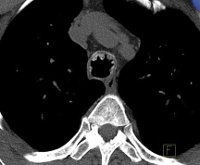

• Визуализационных методик. КТ лёгких с виртуальной бронхоскопией позволяет определить зоны высокой плотности в стенках воздухоносных путей, деформацию трахеобронхиального дерева, оценить рельеф слизистой оболочки, обнаружить наличие выступающих внутрь образований. МРТ легких выявляет утолщение бронхиальной стенки, участки обызвествления в её толще.